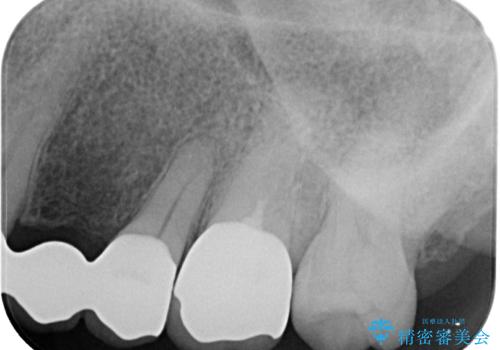

銀歯の下にまでむし歯が及んでおり、レントゲン写真からも神経組織に迫っている状態が確認されました。

稀に冷たいものがしみる程度で、術前診査では神経を全て取る可能性は低いと予想されましたが、一部切除する可能性が高いことを伝えた上で治療を行うこととしました。

やはりむし歯は大きく、一部歯髄を切除することとなりましたが、その後は良好な経過をたどっています。